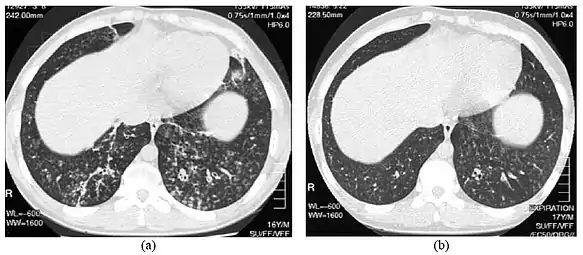

High-resolution computed tomography images of the lower chest in a 16-year-old boy with diffuse panbronchiolitis

The diagnosis of DPB requires analysis of the lungs and bronchiolar tissues, which can require a lung biopsy, or the more preferred high resolution computed tomography (HRCT) scan of the lungs.[7] The diagnostic criteria include severe inflammation in all layers of the respiratory bronchioles and lung tissue lesions that appear as nodules within the terminal and respiratory bronchioles in both lungs.[4] The nodules in DPB appear as opaque lumps when viewed on X-rays of the lung, and can cause airway obstruction, which is evaluated by a pulmonary function test, or PFT.[6] Lung X-rays can also reveal dilation of the bronchiolar passages, another sign of DPB. HRCT scans often show blockages of some bronchiolar passages with mucus, which is referred to as the "tree-in-bud" pattern.[7] Hypoxemia, another sign of breathing difficulty, is revealed by measuring the oxygen and carbon dioxide content of the blood, using a blood test called arterial blood gas. Other findings observed with DPB include the proliferation of lymphocytes (white blood cells that fight infection), neutrophils, and foamy histiocytes (tissue macrophages) in the lung lining. Bacteria such as H. influenzae and P. aeruginosa are also detectable, with the latter becoming more prominent as the disease progresses.[4][5] The white blood, bacterial and other cellular content of the blood can be measured by taking a complete blood count (CBC). Elevated levels of IgG and IgA (classes of immunoglobulins) may be seen, as well as the presence of rheumatoid factor (an indicator of autoimmunity). Hemagglutination, a clumping of red blood cells in response to the presence of antibodies in the blood, may also occur. Neutrophils, beta-defensins, leukotrienes, and chemokines can also be detected in bronchoalveolar lavage fluid injected then removed from the bronchiolar airways of individuals with DPB, for evaluation.[4][9]